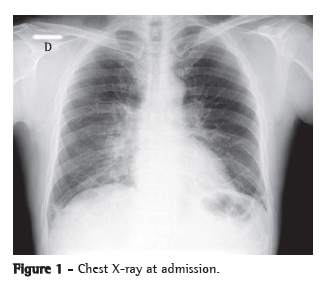

A chest X-ray showed worsening of the bilateral alveolar infiltrate, and a chest CT scan showed multifocal ground-glass infiltrate (Figures 1 and 2).

The most common radiological manifestations of influenza pneumonia consist of reticulonodular opacities, with or without superimposed areas of consolidation. Less commonly, patients with influenza pneumonia can present with focal areas of consolidation, typically in the lower lobes, without apparent reticular or reticulonodular opacities. The radiological abnormalities typically resolve in approximately three weeks. Consolidations can occur due to secondary bacterial pneumonia.(7,8)

On chest CT scans, various patterns are possible. However, the ones most commonly reported are those showing lobular areas, typically bilateral, of ground-glass attenuation. Other possible patterns are the presence of focal areas of consolidation, centrilobular nodules and the tree-in-bud pattern.(9)